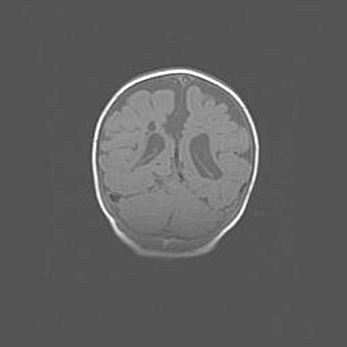

Церебральная ишемия II.

Возраст: 5 дней

Вес: 3400 г

Пол: женский

Окружность головы: 35 см

Срок гестации: 39 недель

Церебральная ишемия – это заболевание, характеризующееся недостаточностью (гипоксией) либо полным прекращением (аноксией) снабжения мозга кислородом по причине закупорки одного или нескольких сосудов. Это приводит к  что метаболическим расстройствам различной степени тяжести в тканях головного мозга, развитию коагуляционных некрозов и гибели нейронов.